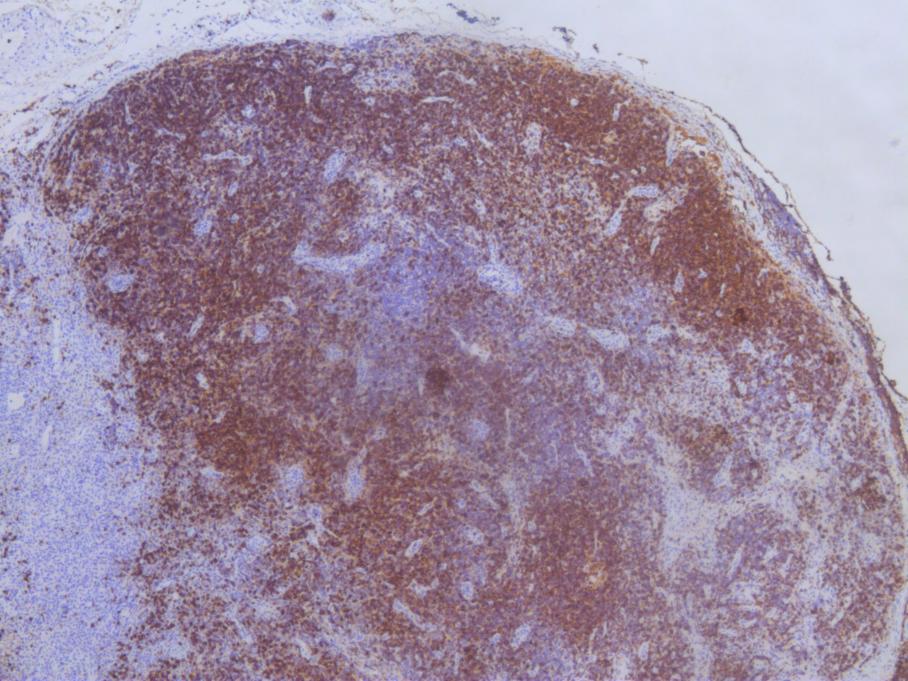

随后,儿科各专业再次会诊,结合专家分析讨论,并与家属多次沟通之后,及时进行了“淋巴结活检 —— 组织细胞学检测”,根据病理结果结合临床表现,最终确诊患儿为“坏死性淋巴结炎”。

组织细胞坏死性淋巴结炎是一种非肿瘤性的以淋巴结肿大为主要临床表现的自限性疾病,因其临床表现无特异性,发病率低,极易漏诊、误诊,只有淋巴组织活检才能确诊。